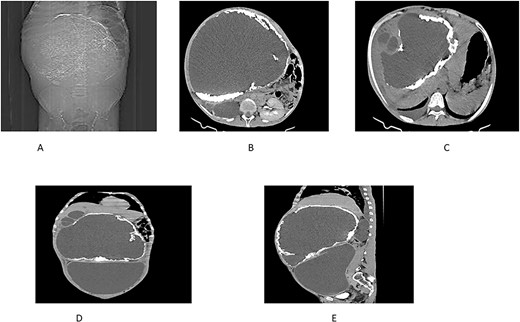

On examination, the patient appeared chronically ill. His vital signs were in normal range except for tachypnea of 48 breaths per minute. Chest examination revealed decreased air entry over the lower posterior one-third of the right lung field. Abdominal examination revealed a grossly distended abdomen (Fig. 1) with a palpable, firm, and non-tender mass measuring 20 × 30 cm.

An abdominal CT scan demonstrated a massive non-enhancing cystic mass with a thick rim of peripheral calcification, measuring 21 × 28 cm, containing peripherally located daughter cysts and pushing the gallbladder anteriorly. Another well-defined, thin-walled, large peritoneal cystic mass, and measuring 13 × 24 × 28 cm, was observed. This mass exhibited fluid attenuation and a focal anteroposterior wall defect, closely apposed to the hepatic cystic mass. It displaced bowel loops, great vessels, and the right kidney posteroinferiorly while mediating the pancreas.

Further findings included pericalyceal dilatation of the right kidney with an atrophied and thinned-out cortex. Additionally, there was a fluid-attenuating collection measuring ~2.3 cm in depth within the right pleural cavity (Fig. 2).

(A) Scout view showing a large intra-abdominal mass with peripheral calcification. (B) Axial view highlighting a hepatic cyst and an atrophied right kidney with a thinned-out cortex. (C) Axial view depicting a right pleural fluid collection, a hepatic cyst, and two active daughter cysts. (D, E) Coronal and sagittal views depicting the hepatic cyst and the peritoneal cyst (white cross).